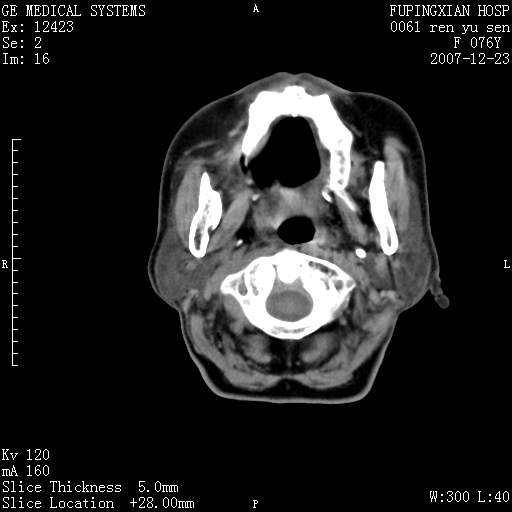

左侧声带是否突出 请关注

喉癌?转移?是否*应考虑

右侧第四磨牙缺失,局部牙槽骨质破坏,边界欠清晰,同侧颌下及竟不见多发肿大淋巴结显示。考虑肿瘤病变可能性大,感染待排